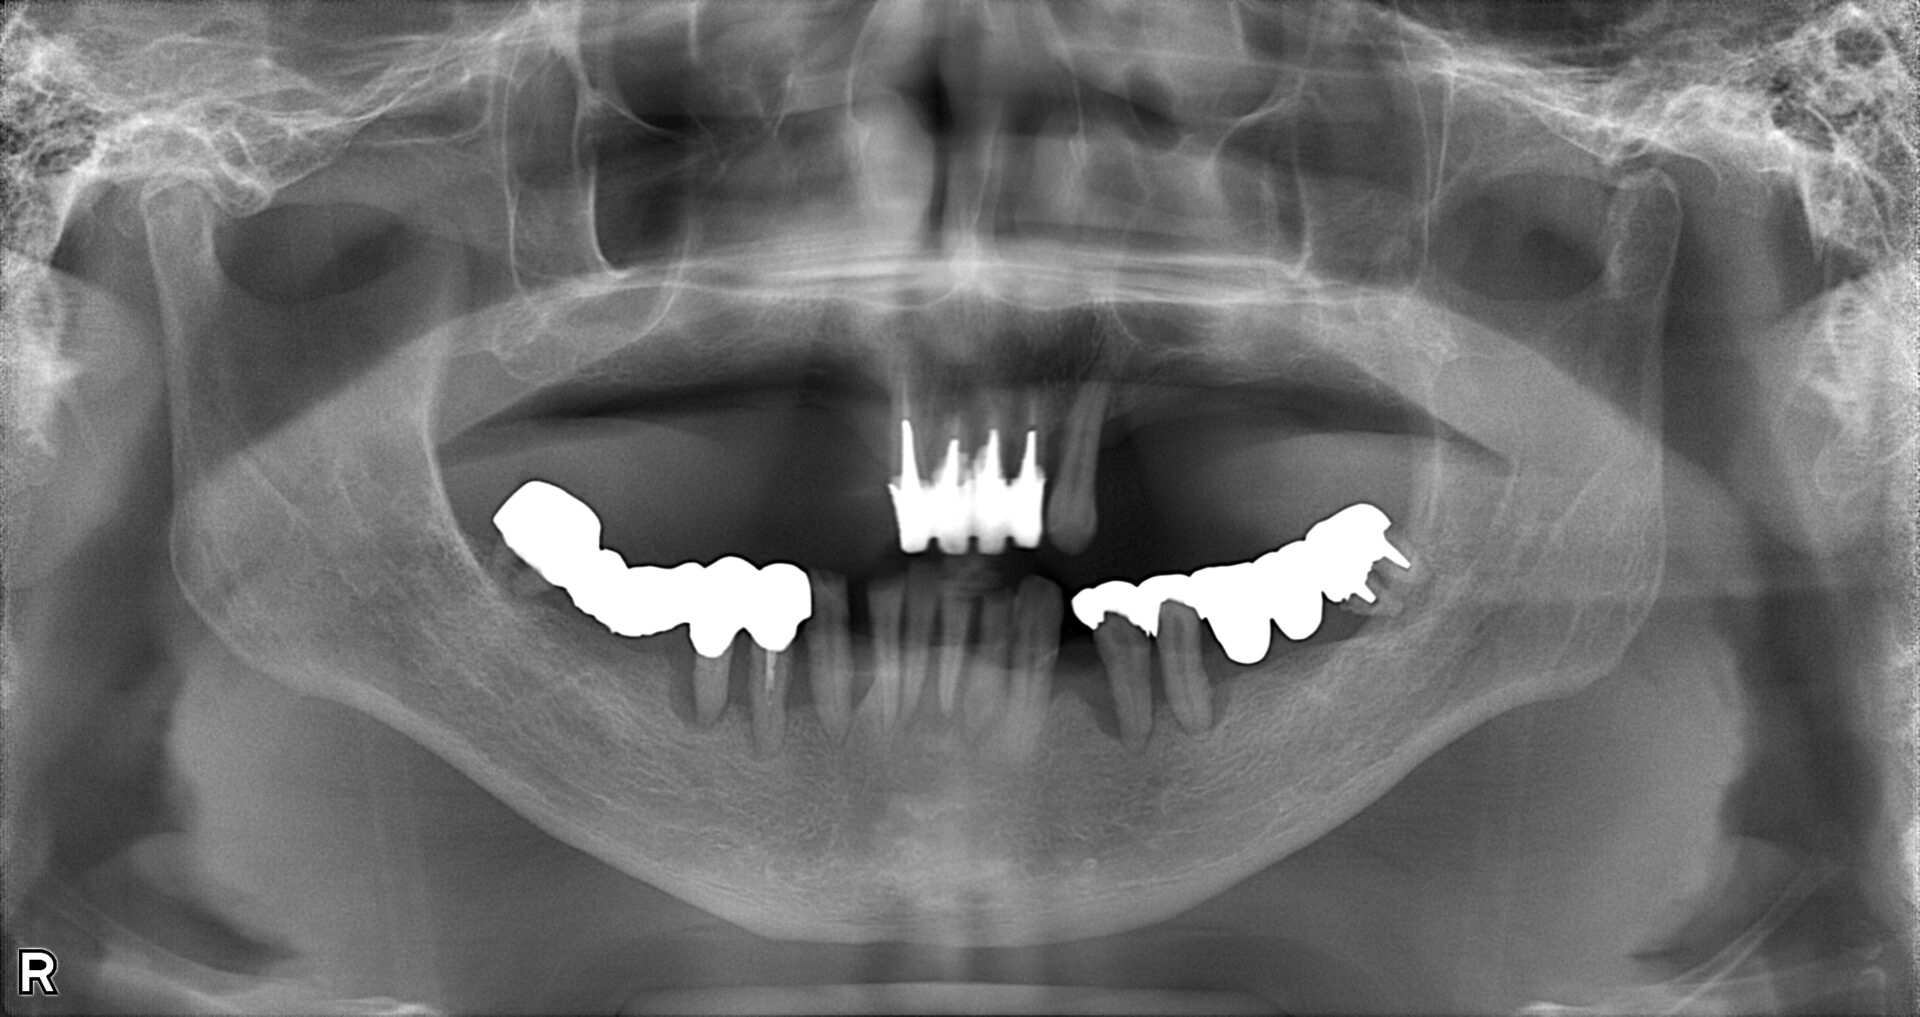

before

after

患者さんの年齢 50代 男性 症状 何も噛めない 治療内容 インプラント治療(オールオン4) 費用 費用900万(税抜) 治療期間・回数 治療期間2年・通院回数12回 メリット なんでも噛めるようになる 見た目が綺麗 デメリット・リスク 骨造成などで費用が増える場合がある - インプラント治療